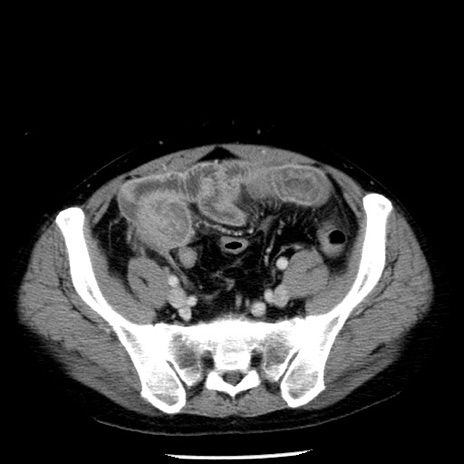

症例29(横断像)

【症例】40歳代男性

【現病歴】2日前から胃痛あり。徐々に周期的な激痛に変化した。本日になっても激痛があるため受診。

【身体所見】意識清明、BT 38-39℃台あり、腹部:膨満、やや硬、右下腹部に圧痛あり。

【データ】WBC 8500、CRP 23.26